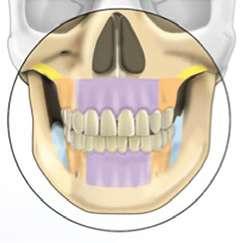

3. Análisis radiográfico y tomográfico (Ilustración 4):

 Constricción maxilar con deficiencia transversal

> 5 mm.

 Clase III esquelética.

 Patrón esquelético hiperdivergente con el plano oclusal mandibular compensado con rotación anti-horaria.

 Sutura palatina media parcialmente osificada (8) (9).

 Posición de terceros molares no favorable, por lo que se recomendó extracción.

El objetivo principal de este tratamiento fue la corrección de la discrepancia maxilar transversal esquelética (> 5 mm), seguida de la corrección vertical y sagital, para lograr una relación oclusal funcional y estable (10).